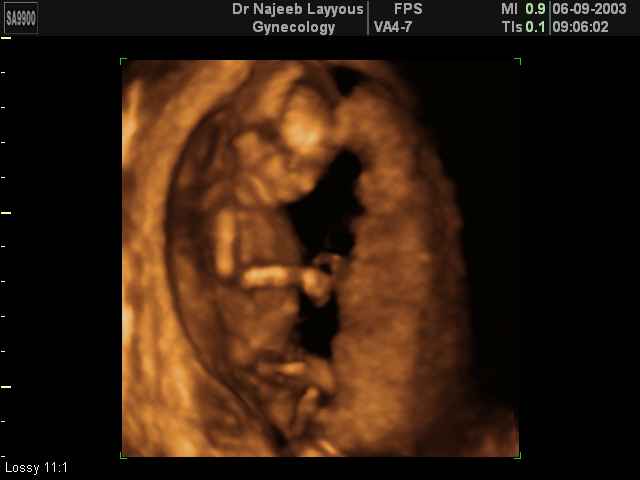

- تصرفات الجنين داخل الرحم

- صور لتصرفات الجنين داخل الرحم

- صور للجنين في المراحل المتوسطة من الحمل

صور لتصرفات الجنين داخل الرحم بجهاز الالتراساوند ثلاثي الأبعاد | الدكتور نجيب ليوس